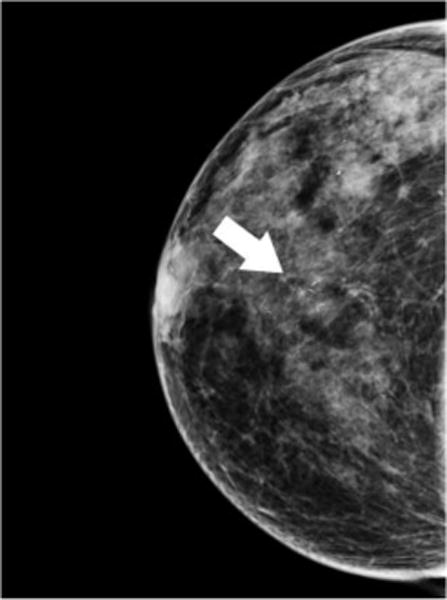

Fig. 1. Ductal Carcinoma In-situ.

64 year-old woman presents for screening mammogram. Mammographic CC (A) and MLO (B) views demonstrate grouping of pleomorphic calcifications in the left breast at the 12 o’clock position (arrows). Reformatted non-enhanced CBCT images at 0.273 mm standard resolution (C) and 0.122 mm high-resolution (D) clearly depict grouping of calcifications; morphology of calcifications are more clearly depicted in the higher resolution images. Lesion diagnosed as DCIS at time of biopsy.